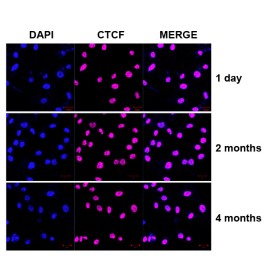

| IF analysis of CD31 (GB12063). Sample: Mouse lung (Paraffin), 4% PFA (G1101) 12-24h. Antigen retrieval: Citrate buffer (pH 6.0) (G1201), pressure cooker 2min. Blocking buffer: 3% BSA in PBS (GC305010), RT, 30min. Primary antibody: 1: 600, 4°C overnight. Secondary antibody: Cy3 conjugated Goat Anti-mouse IgG (H+L)(GB21301),1: 200 RT 1h. |

| IF analysis of CD31 (GB12063). Sample: Mouse lung (Paraffin), 4% PFA (G1101) 12-24h. Antigen retrieval: Citrate buffer (pH 6.0) (G1201), pressure cooker 2min. Blocking buffer: 3% BSA in PBS (GC305010), RT, 30min. Primary antibody: 1: 600, 4°C overnight. Secondary antibody: Cy3 conjugated Goat Anti-mouse IgG (H+L)(GB21301),1: 200 RT 1h. |

| IF analysis of CD31 (GB12063). Sample: Rat lung (Paraffin), 4% PFA (G1101) 12-24h. Antigen retrieval: Citrate buffer (pH 6.0) (G1201), pressure cooker 2min. Blocking buffer: 3% BSA in PBS (GC305010), RT, 30min. Primary antibody: 1: 600, 4°C overnight. Secondary antibody: Cy3 conjugated Goat Anti-mouse IgG (H+L)(GB21301),1: 200 RT 1h. |

| IF analysis of CD31 (GB12063). Sample: Rat heart (Paraffin), 4% PFA (G1101) 12-24h. Antigen retrieval: Citrate buffer (pH 6.0) (G1201), pressure cooker 2min. Blocking buffer: 3% BSA in PBS (GC305010), RT, 30min. Primary antibody: 1: 600, 4°C overnight. Secondary antibody: Cy3 conjugated Goat Anti-mouse IgG (H+L)(GB21301),1: 200 RT 1h. |

| IF analysis of CD31 (GB12063). Sample: Rat lung (Paraffin), 4% PFA (G1101) 12-24h. Antigen retrieval: Citrate buffer (pH 6.0) (G1201), pressure cooker 2min. Blocking buffer: 3% BSA in PBS (GC305010), RT, 30min. Primary antibody: 1: 600, 4°C overnight. Secondary antibody: Cy3 conjugated Goat Anti-mouse IgG (H+L)(GB21301),1: 200 RT 1h. |